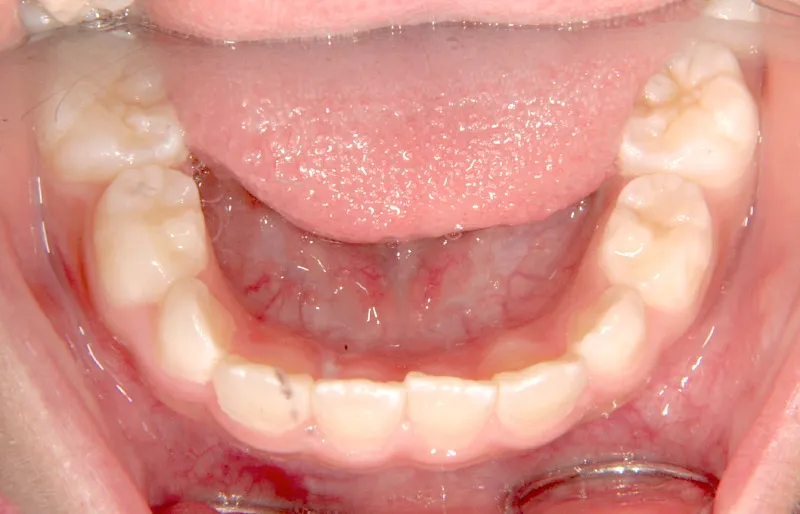

【子供の矯正(一期)】叢生・開咬・前歯で噛めない・舌癖・7歳女児【M.O様】

初診時年齢 小学校1年生 (女性) 主訴 前歯で噛めない

診断名 叢生・開咬 装置名

拡大床

状態 永久歯が生える隙間がない(叢生)

前歯で噛めない(開咬/オープンバイト)

舌の癖によって下の前歯が出て、上の前歯が短いです。

取り外し式の装置で上下の歯並びを拡げて、下の前歯を引っ込めます。

初診